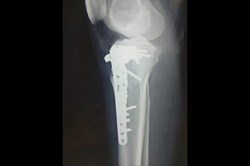

Distal Femur